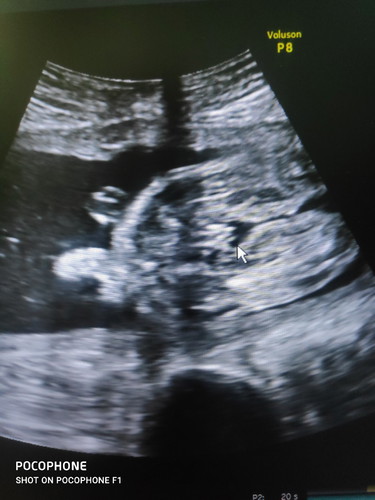

คุณแม่ทุกคน เห็นเป็น หญิงหรือ ชายคะ

ซาวด์ แล้วลูกหลับคะ เลยเห็นแค่นี้ หมอบอกเเนวโน้มเป็น หญิงคะ แต่เราดูไม่ออก?

คล้าย 👧 ตรงลูกศรที่ชี้ไว้ค่ะ